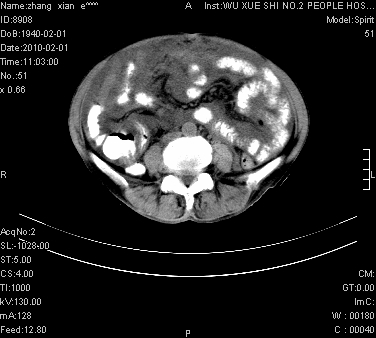

标题: CT24434:70岁 女 腹胀,腹水原因待查 [打印本页]

标题: CT24434:70岁 女 腹胀,腹水原因待查

大量腹水,脾脏囊性占位,子宫颈占位,右侧腹股沟淋巴结肿大,建议+c,先查妇科。

腹盆腔大量积液,子宫增大,子宫颈增大外形不规则,内见低密度影,膀胱后壁显示不清,右腹股沟肿大淋巴结,脾脏囊性占位,子宫颈占位,子宫颈癌?建议增强。

考虑:1、腹膜转移,大量腹水;

2、脾占位性病变;

3、左侧卵巢占位性病变,建议增强进一步检查。

大量腹水,右肾、脾囊肿可能性大          考虑左侧附件区占位,建议增强